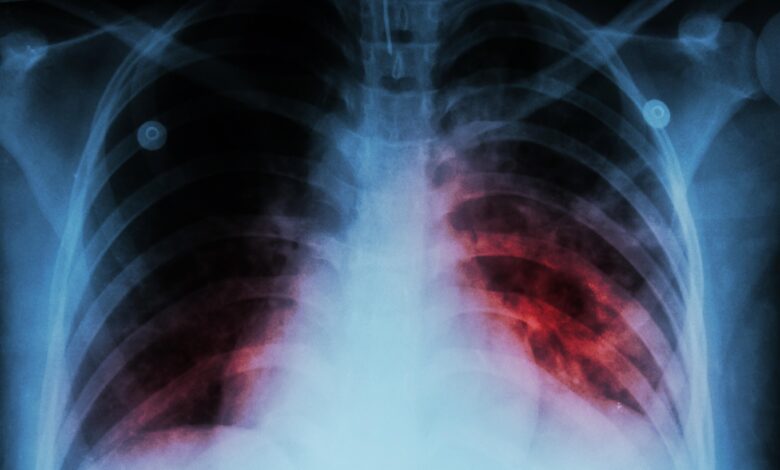

TB usually affects the lungs, but it can also affect other parts of the body, such as brain, kidneys or spine. A person with TB can die if they do not get treatment.

The symptoms of TB disease of the lungs also include coughing, chest pain and the coughing up of blood. Symptoms of TB disease in other parts of the body depend on the area affected. MAF-TB is expected to address the gaps within the TB programming, finding undiagnosed people with TB and linking them to quality care.